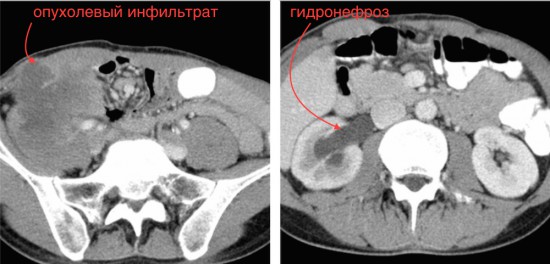

Рецидив рака слепой кишки